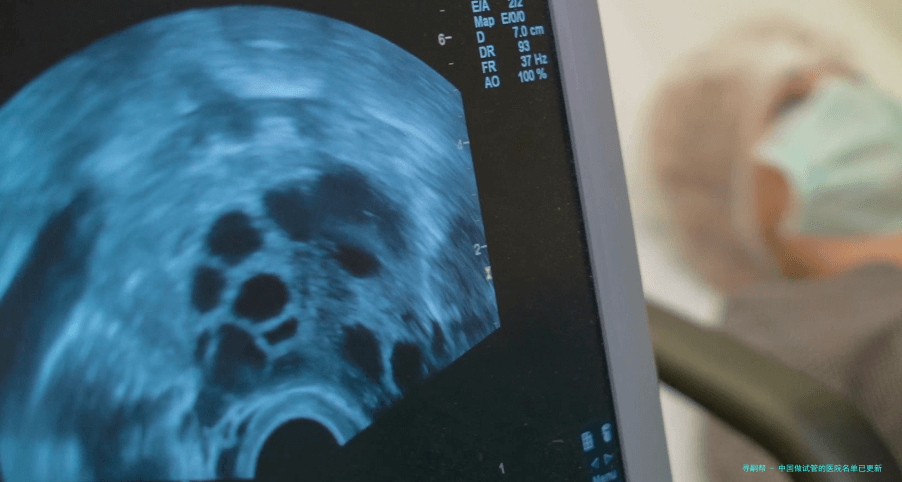

近年来随着社会观点的转变和技术的前行,越来越多的女性抉择通过试管婴儿技术完成生育梦想。对对于一些未婚或单身女性来讲,能否做试管婴儿治疗成为1个关键的问题。固然国家鼓励优育优生,但关于未婚生育的限制依然存在。因而认识哪些医院可以为未婚女性试管婴儿服务显得尤为主要。本文将为您梳理相关信息,但需要再次强调,相关会随时调节,最终以医院实质情况为准,希望能够帮助到您。接下来让我们详细认识一些据谣传可以做试管婴儿治疗而不必结婚证的医院。